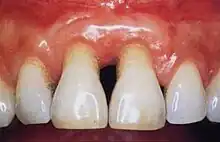

Periodontal recession on maxillary central incisors

The 2018 Disease Classification of Periodontal Diseases and Conditions breaks down the category of periodontitis into three forms and each of these forms are further broken down into two or more subcategories.[7]